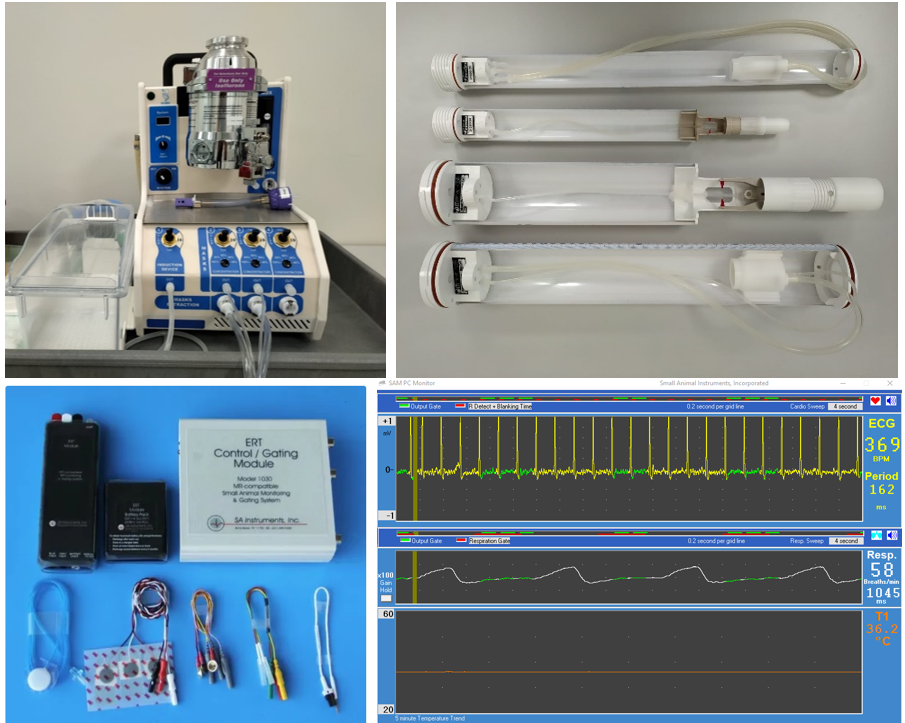

Anestezi için izofluran gaz anestezi cihazı mevcuttur.

Hayvan fizyolojik vital sinyalleri SA Instruments Model 1030 MR uyumlu deney hayvanı monitörizasyon ve sinyal tetikleme sistemi ile takip edilmektedir: EKG, kalıp atm hızı, solunum hızı, vücut sıcaklığı izlenmekte, EKG ve solunum tetikleme ile görüntüleme yapılabilmektedir.

Rat ve fare için özelleşmiş ısıtmalı hayvan yatakları görüntüleme boyunca hayvanların vücut sıcaklığının stabil kalmasını sağlamaktadır. Rat vücut, fare vücut, rat beyin ve fare beyin görüntüleme için hayvan yatakları bulunmaktadır: kafa yatakları hayvanın mükemmel sabitlenmesini sağlayarak solunum tetikleme olmaksızın beyin görüntüleme işlemlerine olanak tanımaktadır.